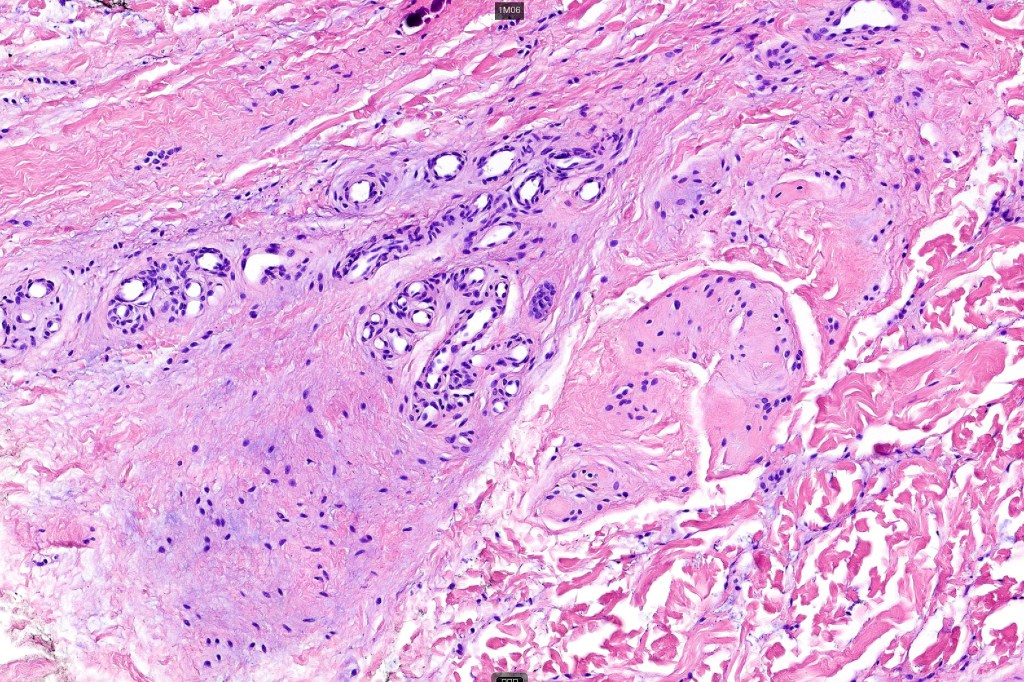

Histological features

•Mid- to deep dermal lobular infiltrate of sweat glands & ducts accompanied by capillaries & small vessels

•In some cases, larger venules & veins are present & associated arteriovenous malformation, spindle cell hemangioma, angiokeratoma & verrucous hemangioma have been described

•Variable adipose, smooth muscle, neural & apocrine components